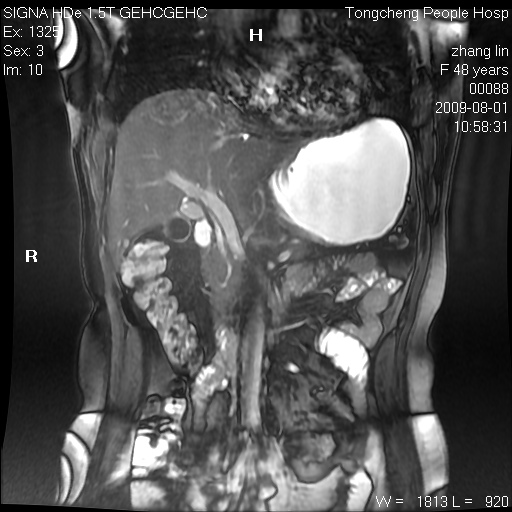

女,48岁。健康体检,彩超发现右肾占位性病变。平素健康。

临床诊断:右肾占位性病变,性质待定(囊肿?肿瘤?)。

上中腹部mr平扫+增强扫描,图像如下:

右肾上极见一类圆形病灶,t1wi呈等信号t2wi呈等高混杂信号,三期增强无强化,边界清---考虑囊肿出血。

同反相位均表现为等信号,病变无强化,考虑含蛋白的囊肿可能,弥散加权相或许有些帮助,

肝囊肿

慢性胆囊炎